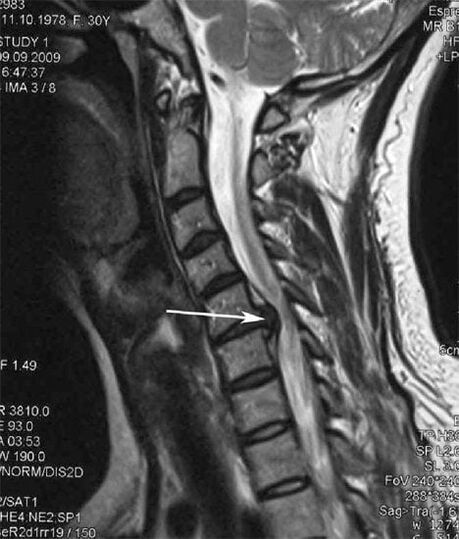

In the early stages, osteochondrosis is detected by MRI.Later, the pathology can be diagnosed by x-ray.On x-rays of the cervical spine, a decrease in the distance between the vertebrae, pathological changes in the facet joints and osteophytosis become noticeable.

| Cervical osteochondrosis | The appearance of pathological changes in one or more segments of movement of the spine.Impaired spinal mobility, development of myofascial pain syndromes and spinal root pinching | Pain, paresthesia and motor disturbances in the cervical region, which spread to the back of the head and upper limbs.Detection of characteristic changes in the spine on MRI and X-rays (osteophytes, decrease in the distance between the vertebrae, signs of damage to the intervertebral joints) |

Many people complain of not being able to turn their neck due to severe pain that appears after suddenly lifting something heavy.This phenomenon indicates the formation of a herniated disc.The cause of pain in the back, neck and upper limbs is pinching of one of the nerve roots emerging from the spinal cord.